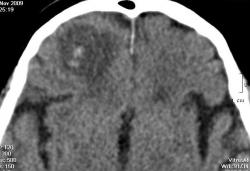

Мужчина, 70 лет. На охоте споткнулся о заячью ловушку, упал на сучок. В результате проникающий оскольчатый перелом крыши орбиты, контузионный очаг (черные стрелки) в лобной доле с небольшими кровоизлияниями (красные стрелки), пузырек воздуха (голубая стрелка).